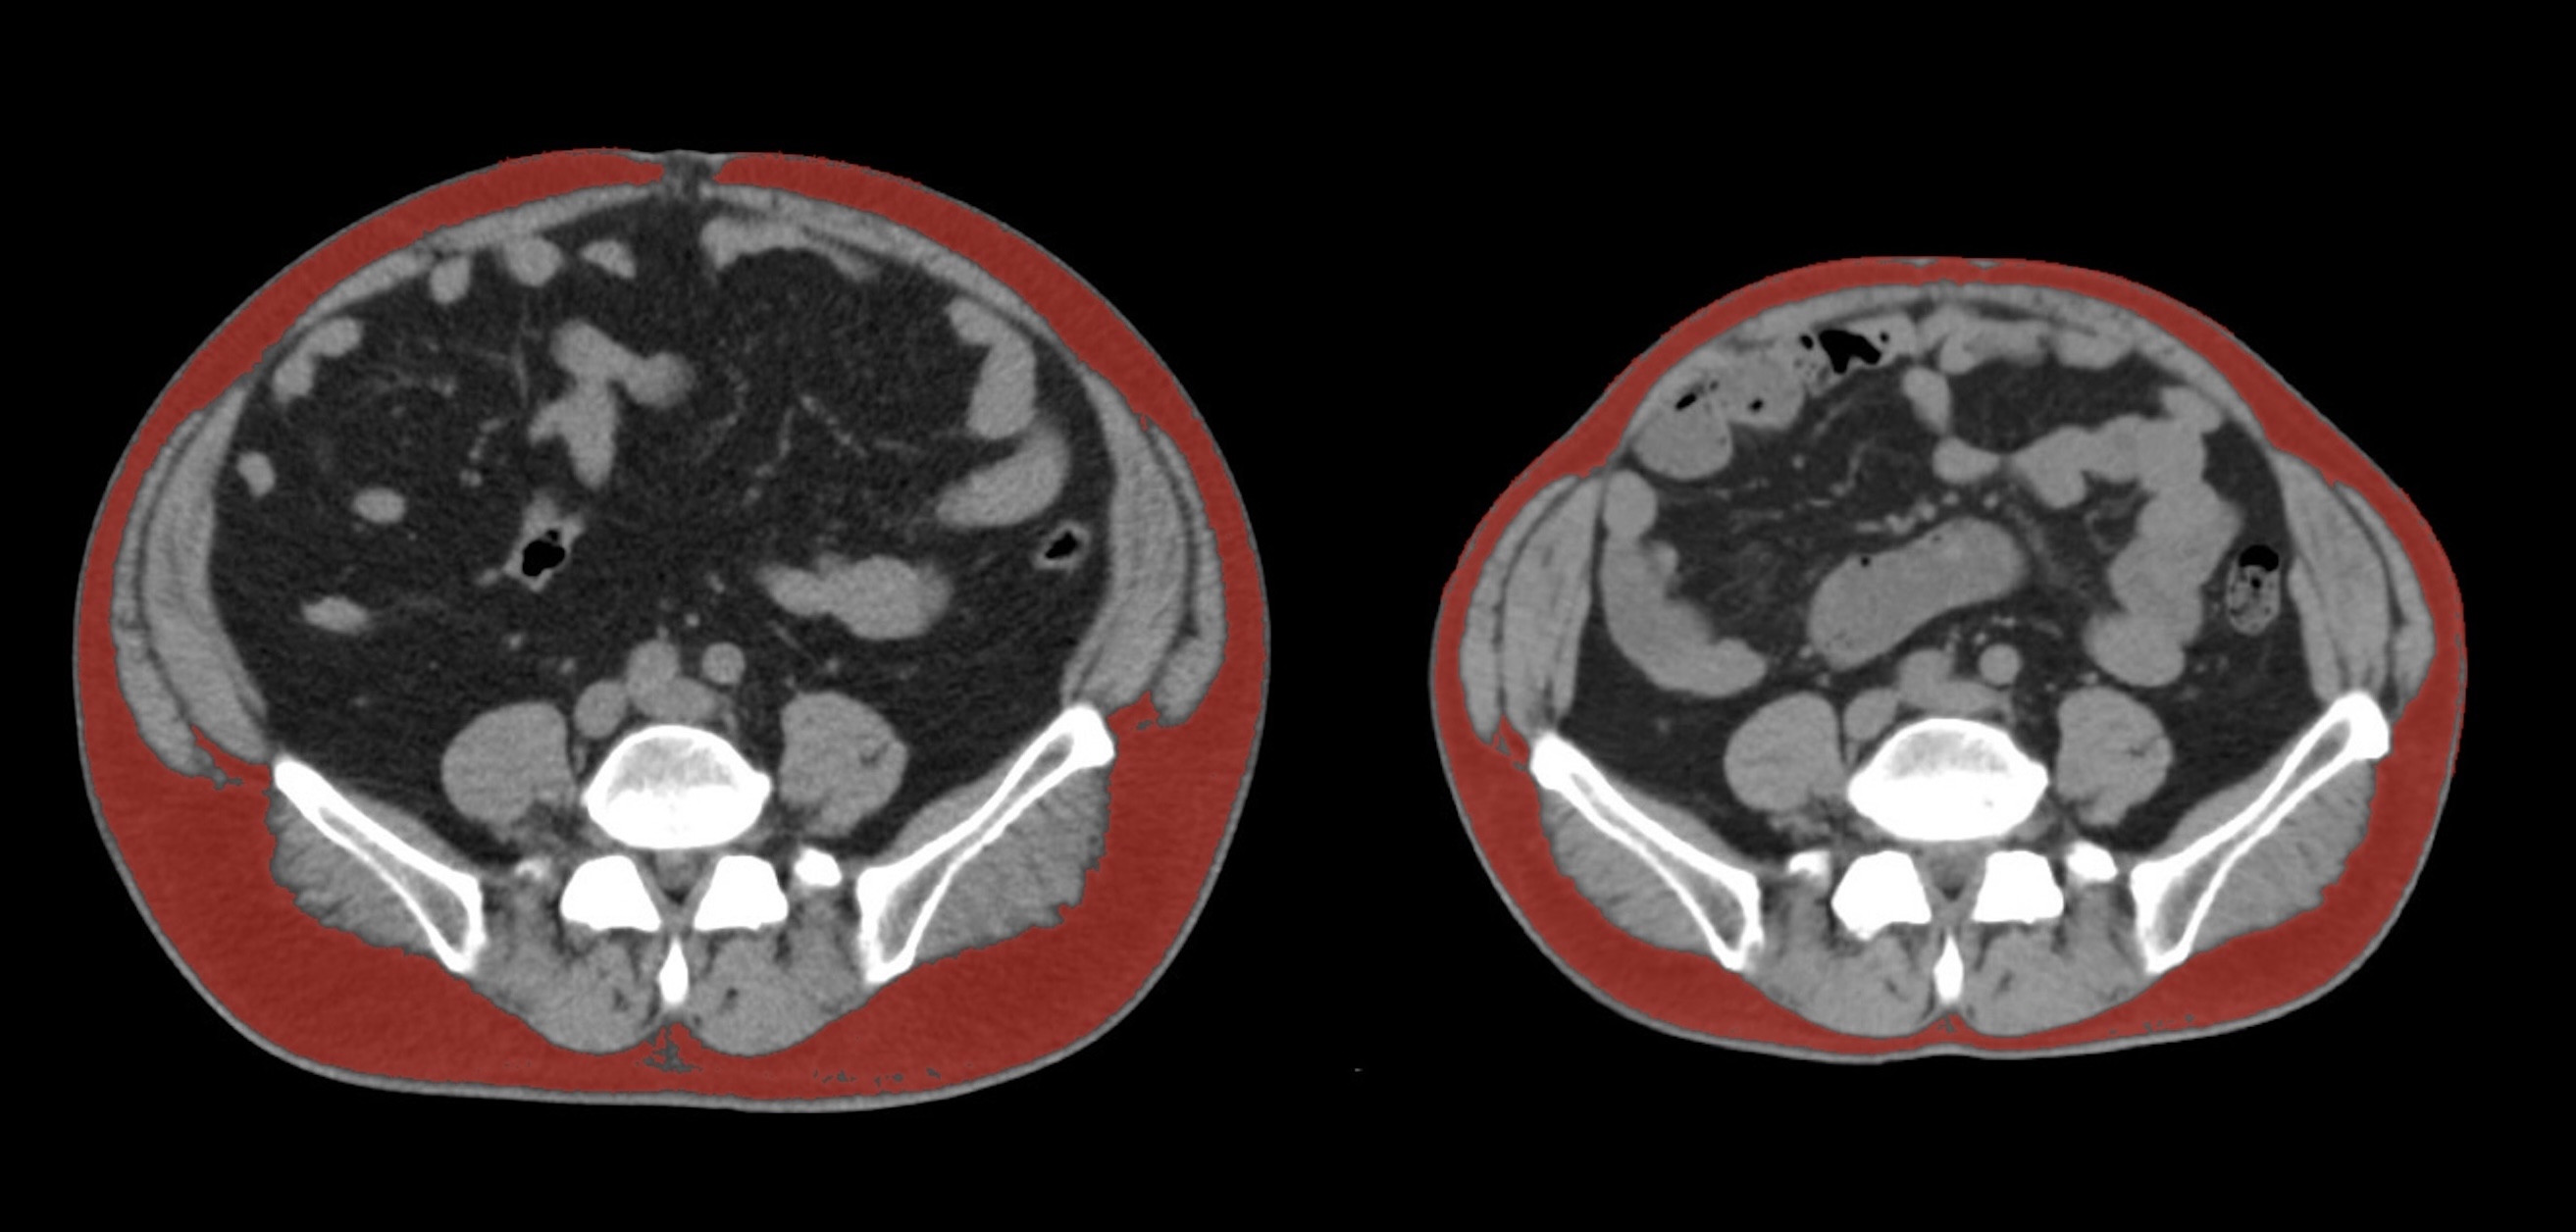

①

50代・女性(ご本人のご厚意で画像提供)

治療内容:チルゼパチド7.5mgの週1回自己注射による脂肪減少と脂肪肝改善

治療期間: 12ヶ月(52週)((用量は2.5mgから開始し最大で15mg。減量効果が得られる必要用量には個人差があります。))

費用:自由診療の場合は9900円(税込)×52(週)=514800円

想定されるリスク・副作用:下記に副作用を記載

※医療広告ガイドラインに準拠して表記

1:脂肪の減少

皮下脂肪の減少(赤色部分)